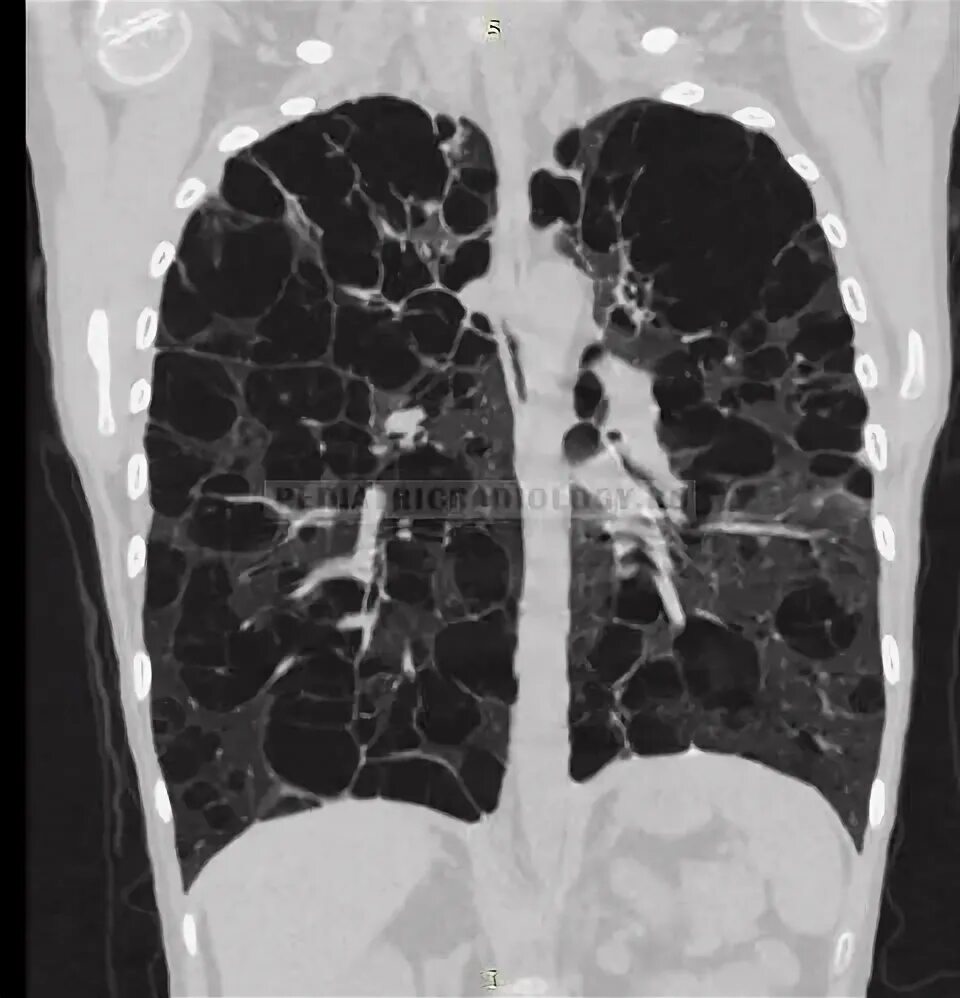

Кт х